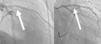

Transthoracic echocardiogram showed a depressed left ventricular ejection fraction of 34% with apical akinesia, no valve diseases, and no visible thrombi. Coronary angiography showed proximal and medial left anterior descending occlusions caused by a massive thrombus (Figure 1, panel A; moving angiograms in supplementary materials). Circumflex and right coronary arteries were normal. In view of the history of thrombophilia, coronary angioplasty was not initially performed and antithrombotic treatment combining anticoagulation with unfractionated heparin (monitored by anti-Xa activity, targeting 0.3 to 0.7 IU/mL) and dual antiplatelet therapy was initiated. A second coronary angiogram was performed after five days of antithrombotic treatment and showed complete regression of the thrombus with an underlying normal left anterior descending artery (Figure 1, panel B). However, an intravascular ultrasound study (IVUS) revealed an atheromatous plaque (Figure 2). Thus, we hypothesized that two mechanisms were in play: the rupture of an atheromatous plaque initiating an anterior myocardial infarction aggravated by his mixed coagulopathy (Protein C deficiency associated with Factor V Leiden mutation).